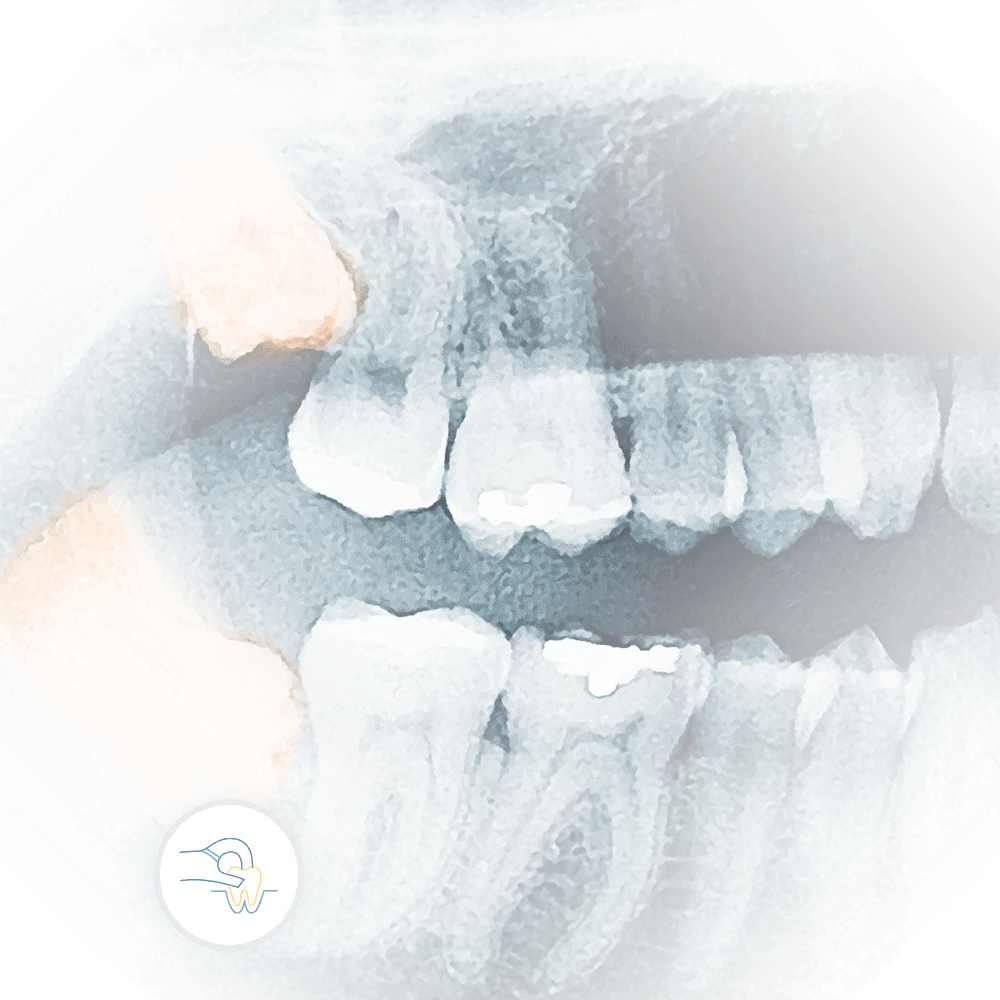

Scene in a dental office showing a male dentist in black scrubs and blue surgical mask analyzing a dental X-ray on a monitor, pointing at the image.

Scene inside a modern dental office, where a male dentist in black scrubs and a blue mask is engaged in a discussion with a patient or colleague, pointing at a dental X-ray displayed on a monitor, highlighting details of the dental structure.